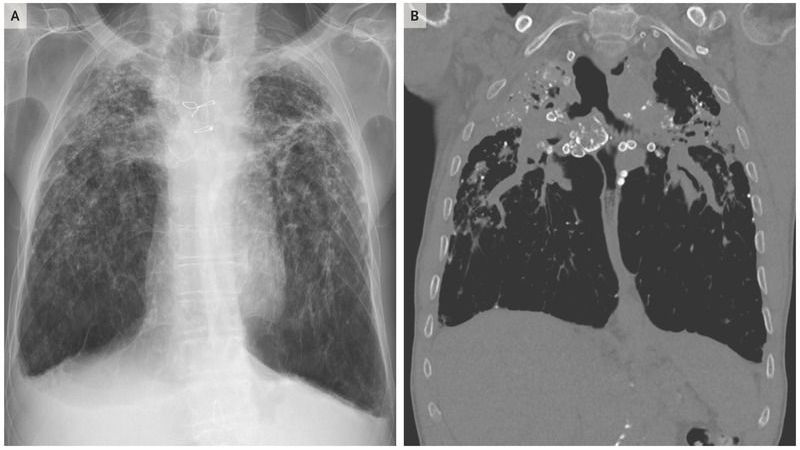

A 76-year-old man presented to the pulmonary clinic with a 6-month history of progressively worsening dyspnea and productive cough. The patient had never smoked; 40 years earlier, he had worked as a sandblaster for 7 years. Physical examination was notable for diminished breath sounds and diffuse inspiratory rhonchi. Findings on radiography (Panel A) and computed tomography (Panel B) of the chest included numerous calcified nodules, eggshell calcifications, and coalescence of apical opacities and larger lesions characteristic of progressive massive fibrosis with upper-lobe volume loss. A diagnosis of chronic silicosis with progressive massive fibrosis was made. Chronic silicosis may develop many years after the inhalation of respirable crystalline silica and is associated with a range of occupations, including mining, foundry work, cement and concrete production, sandblasting, masonry, and ceramic production. Nodules typically occur in the upper zones of the lung. There are no specific therapies for chronic silicosis, except for avoidance of silica in the environment. During 3 years of follow-up, the patient had progression of dyspnea with decreasing exercise tolerance.